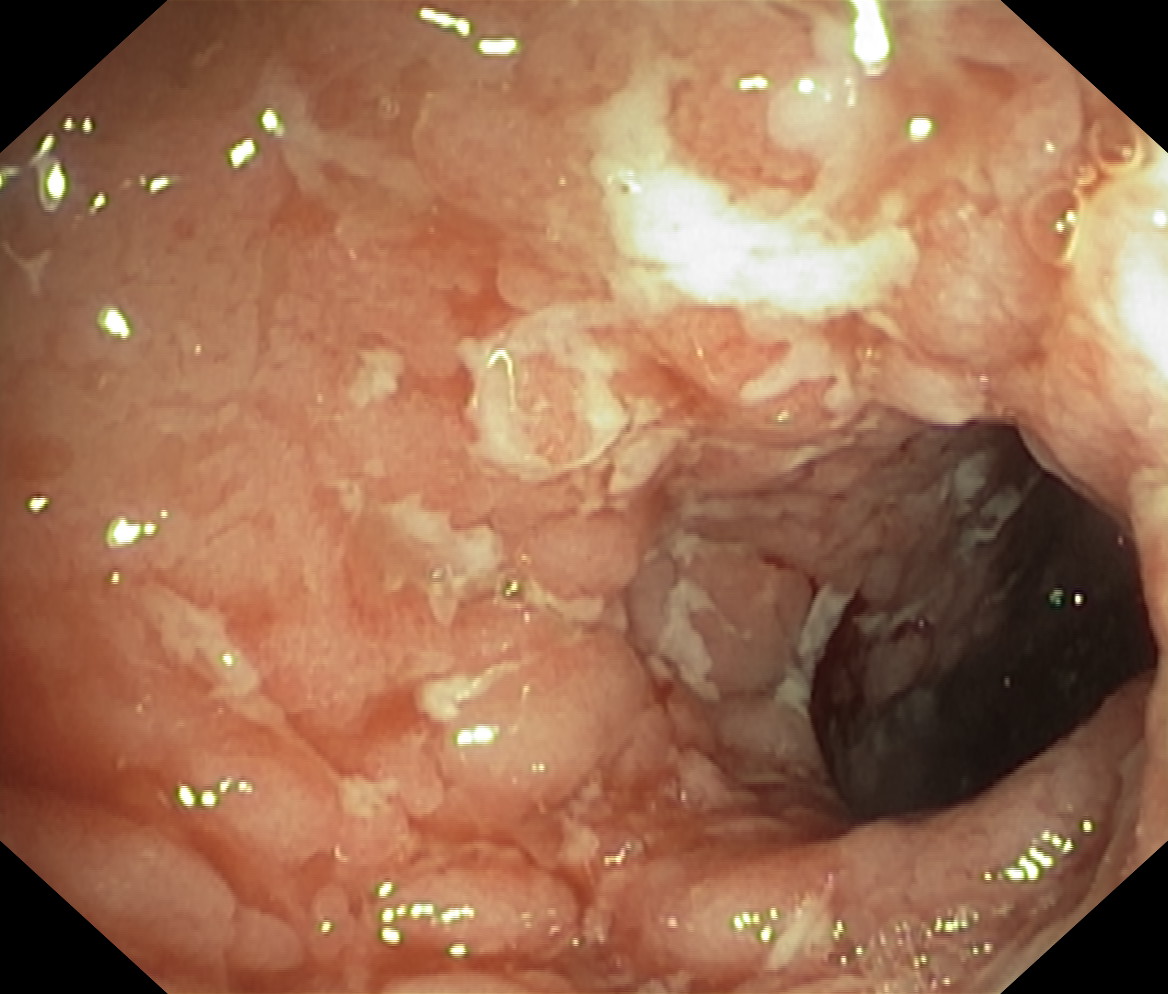

Choroba Leśniowskiego-Crohna